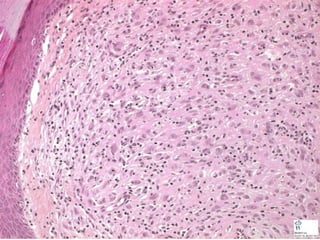

• #57 Benign fibrous histiocytoma, or dermatofibroma

• #58 Benign fibrous histiocytoma, or dermatofibroma